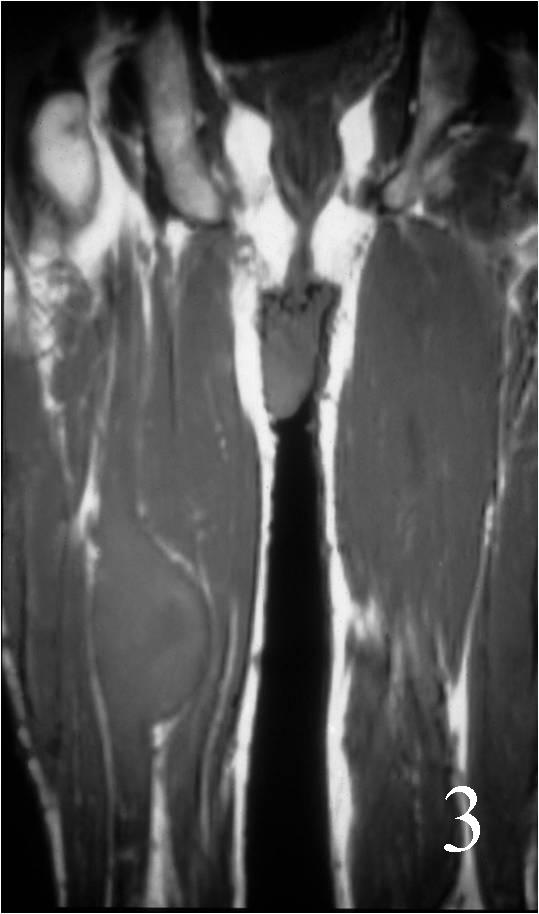

- Isointense to higher signal than muscle on T1W (Fig. 2, 3)

MRI of the thigh, showing a heterogeneous soft tissue lesion in the posterior compartment of the thigh on axial (Fig. 2) and coronal (Fig. 3) T1W images. The addition of gadolinium contrast shows enhancement in the periphery of the mass with necrosis and hemorrhage in the center of the mass typical of a high grade sarcoma (Fig. 4 and 5)